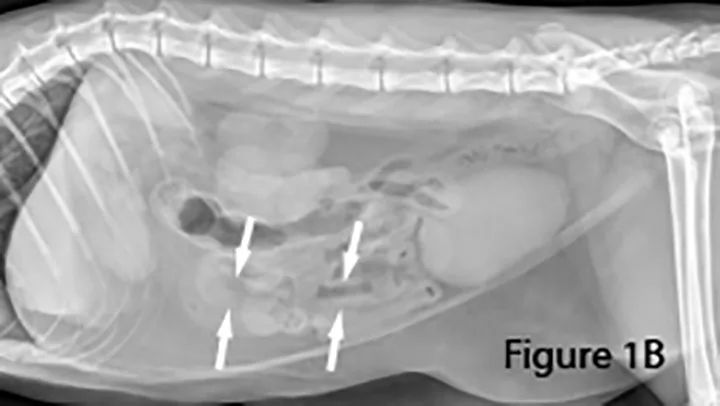

Lateral abdominal radiograph of a dog with small intestinal obstruction. There is marked segmental small intestinal dilation (arrows) with heterogeneous soft tissue and mineral opaque material in the lumen. The cause (ie, the mass) is not identifiable radiographically; there is a large amount of normal empty small intestine.

Focal loss of wall layering and eccentric thickening of the intestinal wall (arrows) are present on ultrasound image showing abnormally dilated small intestinal lumen (L) orad to the mass. Normal empty small intestinal segments are seen in the transverse section in the near field (*). Surgery confirmed diagnosis of mucinous adenocarcinoma.